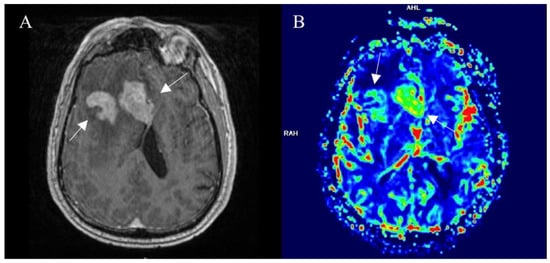

3.3. Perfusion-Based Imaging

3.3.1. Dynamic Susceptibility Contrast